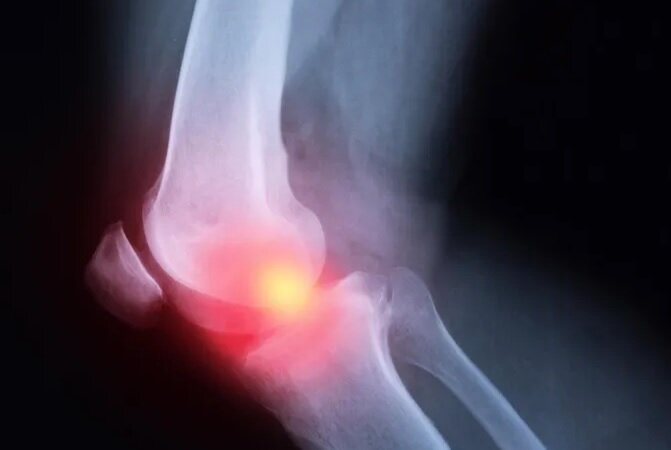

این فوق تخصص ارتوپد افزود: برای تشخیص و درمان جوش خوردگی استخوان، نیاز به یافتههای بالینی و رادیوگرافی و در اغلب موارد نیز نیاز به مداخله جراحی و درمان های کمکی داریم.